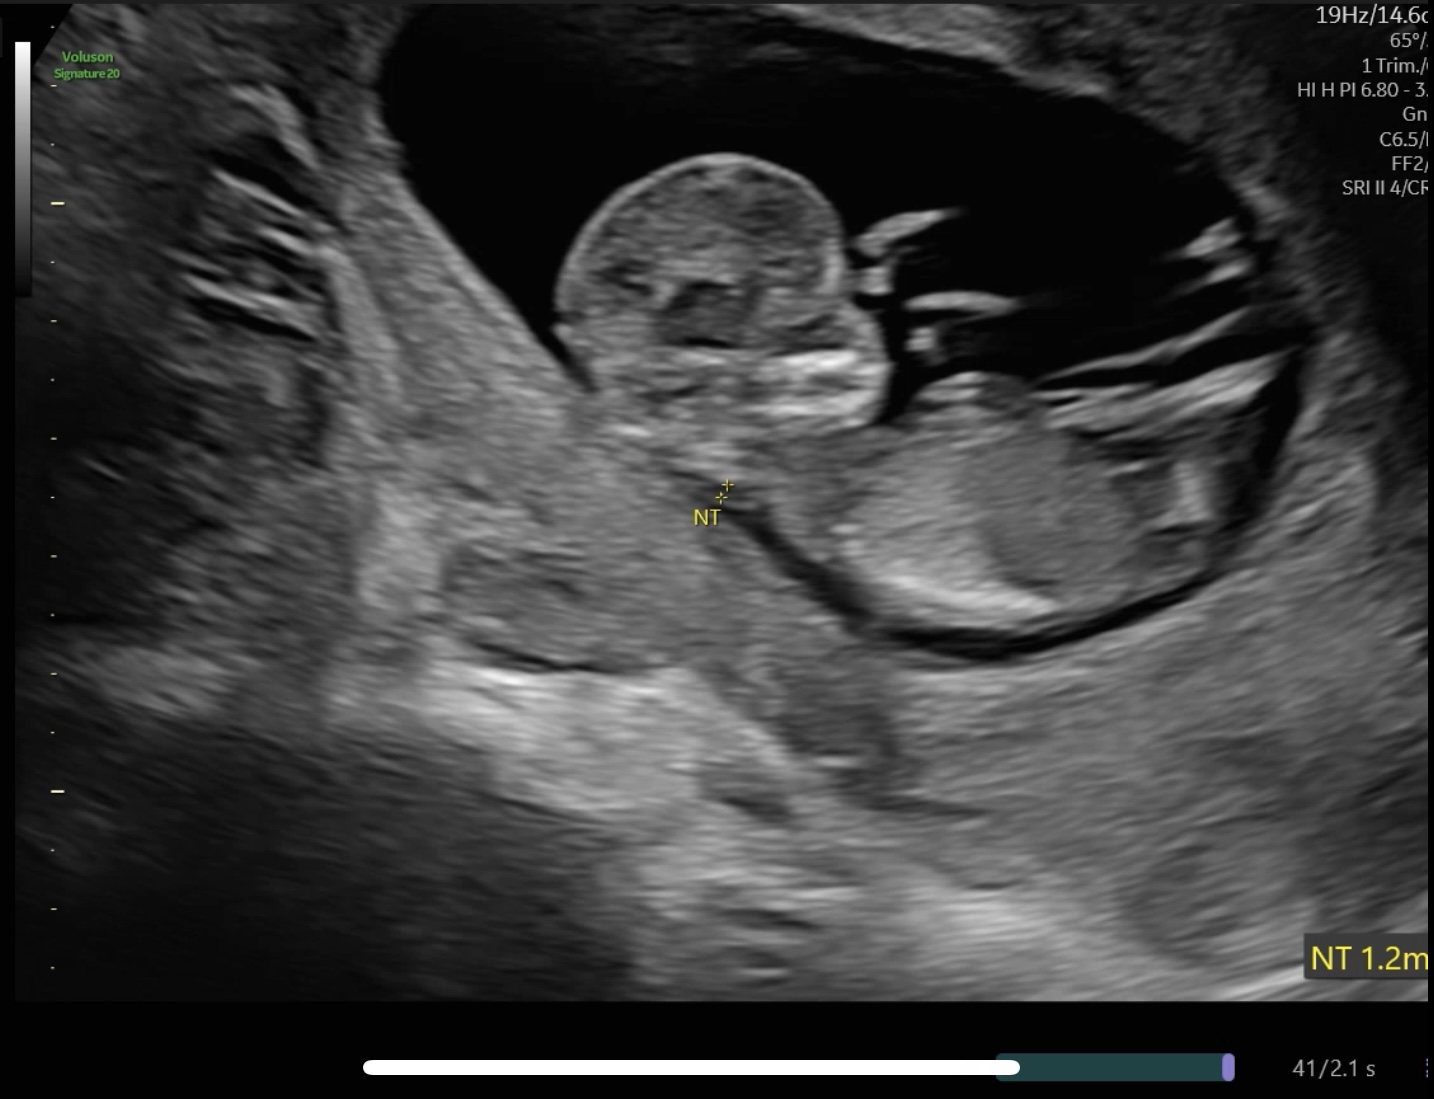

1차 기형아 검사 & 목투명대(NT) 검사

10-13주 사이에 진행되는 1차 기형아 검사는

태아의 다운증후군, 에드워드증후군, 신경관결손

위험도를 평가하는 중요한 검사다.

특히 목투명대 측정은 태아의 목 뒤 투명한

공간의 두께를 초음파로 측정하는 검사인데,

이 두께가 증가할수록 염색체 이상 위험도가

높아질 수 있다.

목투명대 정상 범위는 1.0mm~2.5mm 사이이며,

3.5mm 이상이면 고위험군으로 분류되어

정밀검사나 NIPT 검사가 권유될 수 있다.

12주 2일차에 1차 기형아 검사를 진행하였다.

NT(목투명대) 수치는 1.2mm로 정상 범위로 측정됨.

검사 5일 후, 저위험군이라는 문자 통보를 받았다.

혈액검사 결과와 초음파 소견을 종합적으로

판단한 결과였다.